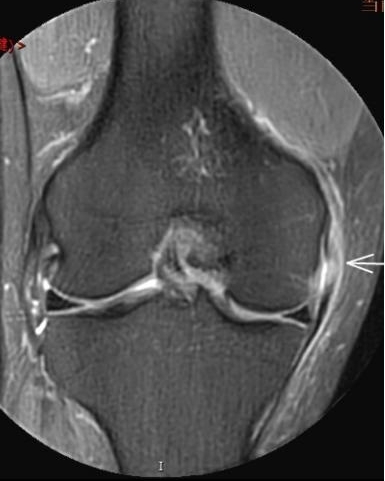

4. 不明腫脹+發(fā)熱——滑膜的“洪水警報(bào)”

場(chǎng)景:膝蓋腫成“發(fā)面饅頭”,皮膚發(fā)燙如“小火爐”

MRI偵查:鑒別痛風(fēng)性滑膜炎、感染或類風(fēng)濕病變,阻止“炎癥風(fēng)暴”

(滑膜增厚、積液)